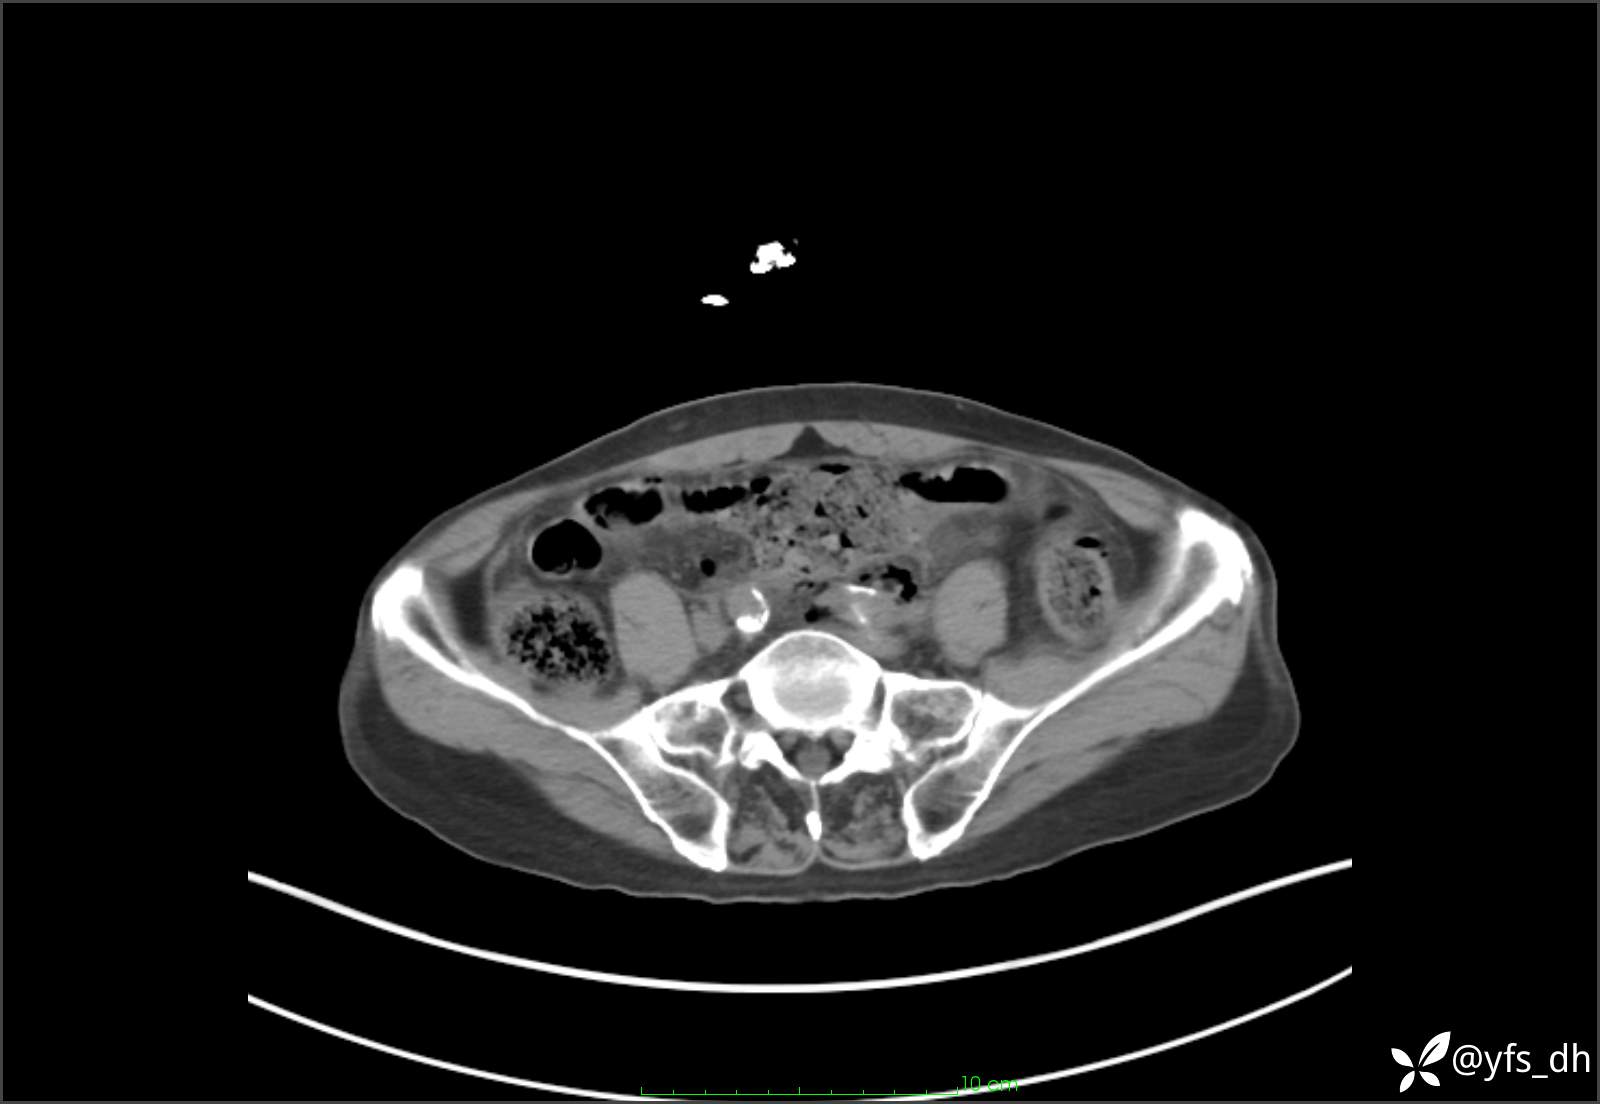

1.简要病史:患者4天前突发上腹部疼痛不适,但可以忍受。3小时前饭后突然加重,不能忍受后就诊。

2.简要手术记录:术中见腹盆腔大量肠液及粪便,乙状结肠中下段见一约3cm的破口。